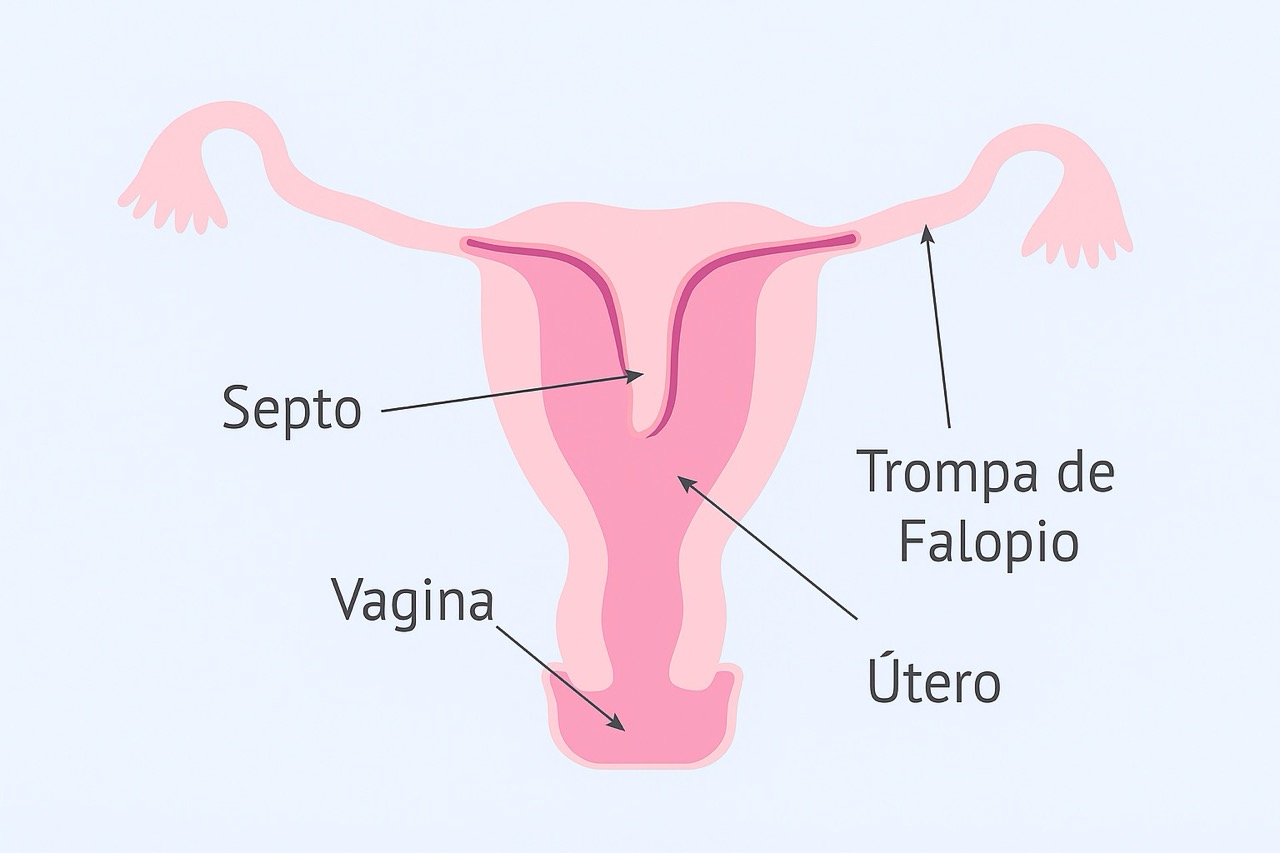

Las adhesiones intrauterinas son bandas de tejido fibroso que se forman dentro de la cavidad del útero, provocando que sus paredes se adhieran parcial o totalmente. Esta condición puede alterar la anatomía uterina normal y afectar la menstruación, la fertilidad y la salud reproductiva.

Estas agresiones pueden generar una cicatrización anormal, dando origen a las adherencias.

La histeroscopía permite visualizar directamente la cavidad uterina y evaluar el grado de las adherencias.

👉 En casos bien tratados, es posible recuperar la anatomía uterina y mejorar el pronóstico reproductivo.